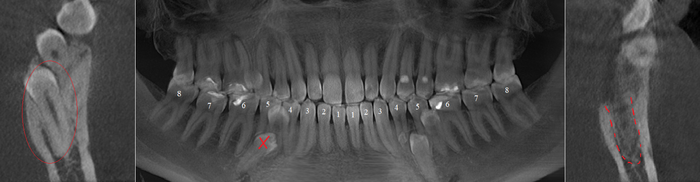

Согласитесь, не особо эстетично. Ортопантомограмма:

Фрагмент компьютерной томографии (вид сбоку):